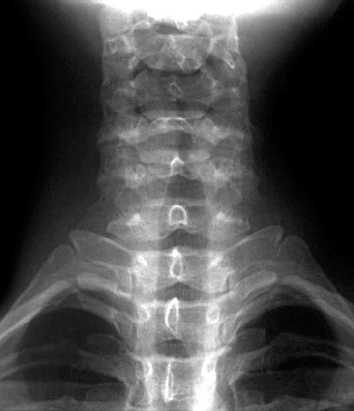

• Body of CIII

• Right 1st Rib

• Spinous Process

• Transverse Process of TI

• Uncovertebral Joints